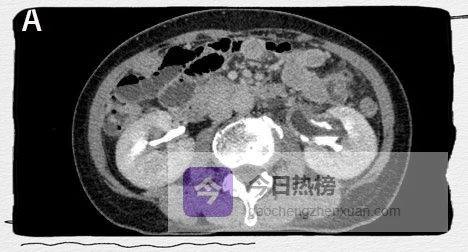

图1A

CT平扫示左肾及左侧输尿管扩张积水。